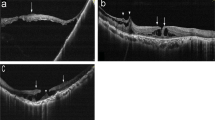

Fifty eyes of from 8 men and 39 women (mean age: 61.0 ± 7.5 years) were enrolled. The mean axial length was 29.42 ± 2.13 mm. The median follow-up time before and after LMH formation was 35 months (range: 5–90 months) and 47 months (range: 13–94 months), respectively. Four types of LMH formation processes were identified, including (1) type 1, LMH developed after foveal avulsion induced by VMT (8 cases) (Fig. 1a, b); (2) type 2, LMH developed after the inner medial wall of a parafoveal cyst or retinoschisis ruptured (32 cases) (Fig. 1c, d); (3) type 3, the ruptured central foveal cysts induced by ERM led to LMH formation (5 cases) (Fig. 1e, f); and (4) type 4, progressive foveal thinning was induced by an ERM, and the LMH formed without an intervening stage of cyst or retinoschisis (5 cases) (Fig. 1g, h). Table 1 shows the clinical characteristics of LMH with different formation processes. Type 2 LMH was the most common (64%). Type 4 LMH had the highest rate (80%) of ellipsoid zone disruption, but no EP. Sixty percent of type 3 LMHs were A-shaped, while V-shaped LMH was the predominant form in other types. In some patients, the LMH initially resembled a “tractional type” LMH and evolved into a “degenerative type” configuration later (Fig. 1i-l). Table 2 shows the changes in the clinical characteristics of LMH during the follow-up. The BCVA of patients with type 2 (P = 0.003, paired Wilcoxon rank-sum test) and type 4 LMHs (P = 0.029, paired Wilcoxon rank-sum test) decreased significantly during follow-up. Among all types, patients with type 4 LMH had the most significant decline (1.03 ± 0.69) of visual acuity (P = 0.024, Kruskal-Wallis test). The vertical depth of type 2 (P = 0.041, paired Wilcoxon rank-sum test) and type 4 (P = 0.017) LMHs increased significantly. The type 4 LMHs had the more significant increase in vertical depth than the type 3 LMHs (P = 0.032, post-hoc analysis of Kruskal-Wallis test). A significant widening of the LMH was seen in type 3 LMHs (P = 0.001, paired Wilcoxon rank-sum test). The RFT of type 2 (P = 0.040, paired Wilcoxon rank-sum test) and type 4 LMHs (P = 0.024) decreased significantly. The type 4 LMHs had the more significant decrease in RFT than the type 1 LMHs (P = 0.015, post-hoc analysis of Kruskal-Wallis test).

a–h Four types of developmental processes of LMH (a, b) Type 1 LMH develops after the avulsion of foveal tissue induced by vitreomacular traction (c, d) Type 2 LMH develops after the disruption of the medial wall of the parafoveal cyst (e, f) Type 3 LMH develops after the deroofing of the central foveal cyst (g, h) Type 4 LMH develops from the progressive central foveal thinning induced by the epiretinal membrane. Intraretinal cyst or schisis is not observed. i–l A representative case of LMH evolved from the “tractional configuration” into “degenerative configuration”. i, j LMH develops from the disruption of the foveal cyst by vitreomacular traction (type 1). k It has the features of “tractional LMH” with foveoschisis and a sharp edge. l Four years later, it has transformed into a “degenerative LMH” with a foveal bump and a round edge (asterisk). m–r The different chronological sequences of the LMH and macular retinoschisis (m, n) Group 1: LMH formed before the development of retinoschisis (o, p) Group 2: LMH and retinoschisis developed concurrently (q, r) Group 3: LMH developed in the presence of retinoschisis.

Half of the patients had macular retinoschisis. According to the chronological sequence of the development of LMH and macular retinoschisis, patients could be categorized into three groups: (1) group 1 (10 eyes), in which the LMH developed first and transformed into LMH with retinoschisis (Fig. 1m, n); (2) group 2 (6 eyes), in which the LMH and retinoschisis developed at the same time (Fig. 1o, p); (3) group 3 (9 eyes), in which the retinoschisis developed first, and the LMH developed later (Fig. 1q, r). Table 1 shows the clinical characteristics of the three groups (group 1–3) and the eyes without retinoschisis (group 0). Fifty percent and 66% of patients with type 1 and 2 LMHs developed retinoschisis, respectively. None of the type 3 or type 4 LMHs were associated with retinoschisis. Eyes in group 2 had longer axial lengths than eyes in group 0 or 1 (P = 0.043). Other clinical characteristics were not significantly different between the groups. In Table 2, patients in group 1 had a significant decrease in visual acuity (P = 0.047) and RFT (P = 0.002), and an increase in vertical extension (P = 0.045) during the follow-up. The between-group comparison of changes in clinical features were all non-significant.

Highly myopic eyes are more susceptible to abnormal posterior vitreous detachment and ERMs [17,18,19]. The posterior hyaloid firmly adheres to the retinal surface, and is connected to the vitreous cortex. ERM can fuse with this membrane or exist between this posterior hyaloid membrane and the retinal surface [5]. The presence of retinoschisis also changes the foveal structure, traction force, and its direction in HM eyes. In the present study, we observed four types of LMH developmental processes. In short, type 1 LMHs started from foveal tissue avulsion caused by abnormal posterior vitreous detachment and mimicked the abortive development of full-thickness MH; type 2 and type 3 LMHs originated from ruptured parafoveal cysts/schisis and central foveal cysts, respectively. Type 4 LMHs were induced by the persistent ERM traction causing progressive central foveal thinning without going through the parafoveal or foveal cyst stages. In the pre-LMH and the early LMH stages, tractional forces from ERM or vitreous adhesion could be identified in all cases, suggesting that traction, instead of degeneration, was the primary mechanism of LMH formation in eyes with HM. Since macular retinoschisis is a common clinical feature in HM, we specifically examined the chronological sequence of LMH formation and the development of retinoschisis. Retinoschisis could develop before, after, or simultaneously with the LMH formation.

We found that LMHs had distinct evolutions and outcomes according to the different developmental processes, and our classification might have some clinical relevance. Patients with the most common type 2 LMH had ERM with foveoschisis or myopic retinoschisis as a pre-LMH condition. Subsequently, the medial walls of parafoveal cysts ruptured and transformed into LMHs. When combined with macular retinoschisis, LMHs deepened, and the RFT decreased during follow-up, accompanied by visual deterioration. Half of the patients experienced anatomical worsening or progression. Type 3 LMHs developed from the deroofing of foveal cysts induced by vitreous traction or ERM. Subsequently, foveoschisis between the outer plexiform layer and the outer nuclear layer might have occurred, and the horizontal width of LMHs increased significantly. Therefore, type 3 LMHs often acquired an A-shaped configuration, which was protective against progression [14]. We postulated the wider base of A-shaped LMH could dissipate the traction force, thus visual function was more likely to be preserved in this type. Type 1 LMH formed by avulsion of the foveal tissue owing to VMT, which was regarded as the abortive form of full-thickness MH. The width of LMHs and RFT remained stable since the traction had been released. In types 1–3 LMHs, avulsion of foveal tissue and disruption of cysts or schistic cavities were accompanied by the partial reduction of traction. In contrast, type 4 LMHs were induced by ERM without an intraretinal cyst stage. The persistent ERM traction acted directly on the fovea, and caused foveal thinning. Hence, the vertical depth of the LMH increased, and the residual foveal tissue became thinner. This type of LMH was prone to visual deterioration, and all progressed to full-thickness MHs.

The observation of the development and evolution of LMHs in HM eyes may have implications in the formation of idiopathic LMHs, of which the classification and definition have been revised several times [2, 3, 10]. Govetto et al. classified this macular lesion into “tractional LMH” and “degenerative LMH” [10]. Hubschman et al. further redefined the LMH-related lesions into “ERM with foveoschisis”, “LMH”, and “macular pseudohole”[3]. “ERM with foveoschisis” corresponds to the “tractional LMH”. The newly-defined “LMH”, comparable to the “degenerative LMH” has round-edged intraretinal cavitation affecting all retinal layers, and is associated with EP [10]. The classification implies the two different pathways of LMH development. However, recent studies have shown that tractional forces play a primary pathogenic role in degenerative LMHs [24, 25]. The VMT or ERM disrupts the Müller cells cone and induces outer retinoschisis. The damage of Henle fibres is followed by the degeneration of photoreceptors and the inner nuclear layer, which results in the formation of degenerative LMH [24]. In our cohort of HM eyes, the tractional forces could be identified in all cases. Different types of tractional forces, their points of exertion, and the net traction direction could lead to distinct formative and evolutionary processes. Clinical features of degenerative type LMH would develop later (Fig. 1i–l). Whether this observation could be applied to idiopathic conditions remains to be determined.